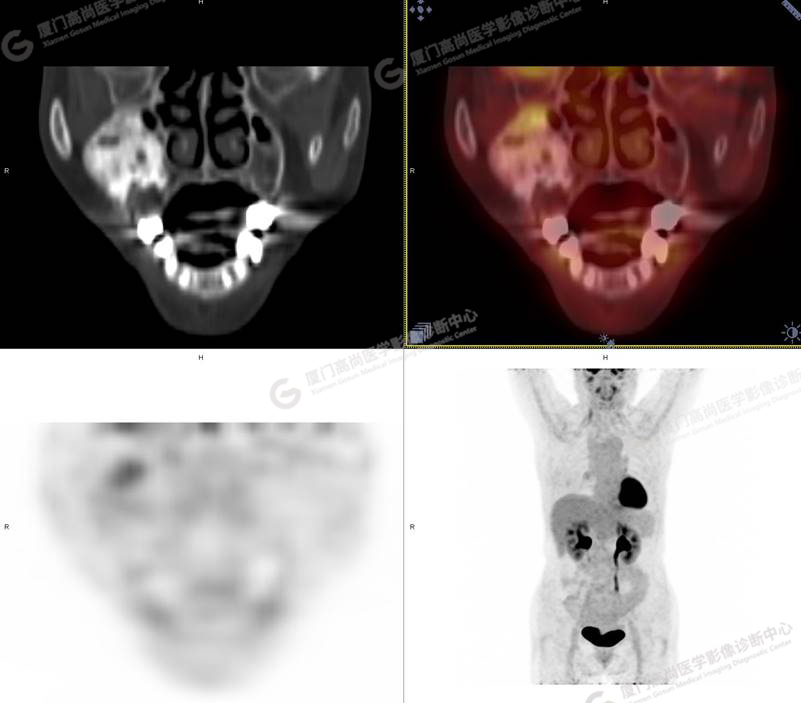

圖1

圖2

圖3

圖4

PET/CT檢查

PET/CT所見:右側(cè)上頜骨、右側(cè)顴骨及右側(cè)額骨骨質(zhì)膨脹,其內(nèi)密度不均勻性增高,部分放射性攝取輕微增高,SUVmax 2.27。